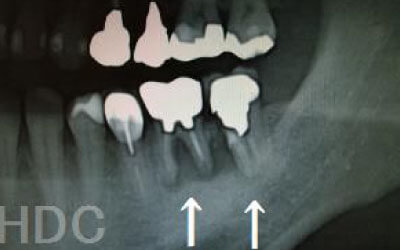

CTでは骨や歯の状態などを3次元で見ることができ、正確な距離を測ることも可能です。

骨の厚みや傾き、神経の位置などを事前にしっかり計測することで安全なインプラントが可能となります。

骨が薄い場合は、そのままインプラントすることはお勧めできません。

ただ、事前に骨を増やす治療をしたり、インプラントと同時に骨を増やす治療をしたりすればインプラントをすることは可能です。

2 神経を傷つけるリスク

顎の骨の中を通っている神経を傷つけるリスクがあります。

ただ、事前にしっかりCT撮影して三次元的に神経までの距離を計測して治療計画を立てれば心配することはありません。

また削りすぎないためのストッパーも当院では使用しております。